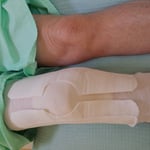

○ 左踵骨骨折(かかとの骨の骨折)

踵の骨折です。脚立から飛び降りた時に受傷しました。レントゲンでは踵骨が割れるように折れています。

通常ですと足の指先から膝まで大きなギプスの固定になりますが、当院で踵に負荷がかからないように土踏まずで体重を支える工夫をしました。これにより歩行が可能になり自宅では松葉つえなくして動き回ることができました。4周経過したころに踵のカップをつくりサポーターで固定、これにより血行もよく足関節の拘縮(固くなること)や

ふくらはぎの筋肉萎縮(細くなること)を防ぐことができました。